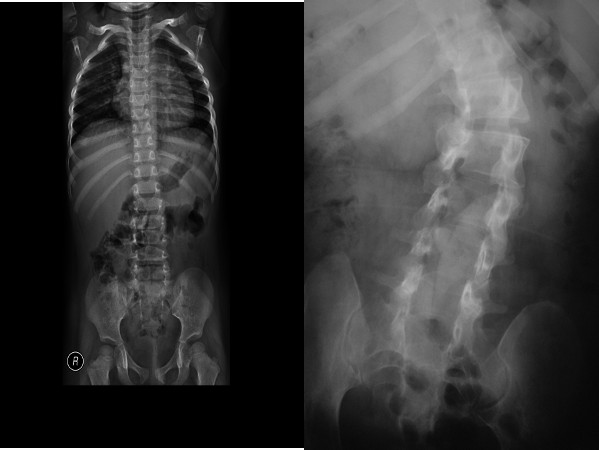

Spina bifida at L5

Spina bifida at multiple vertebral level/spinal dysraphism